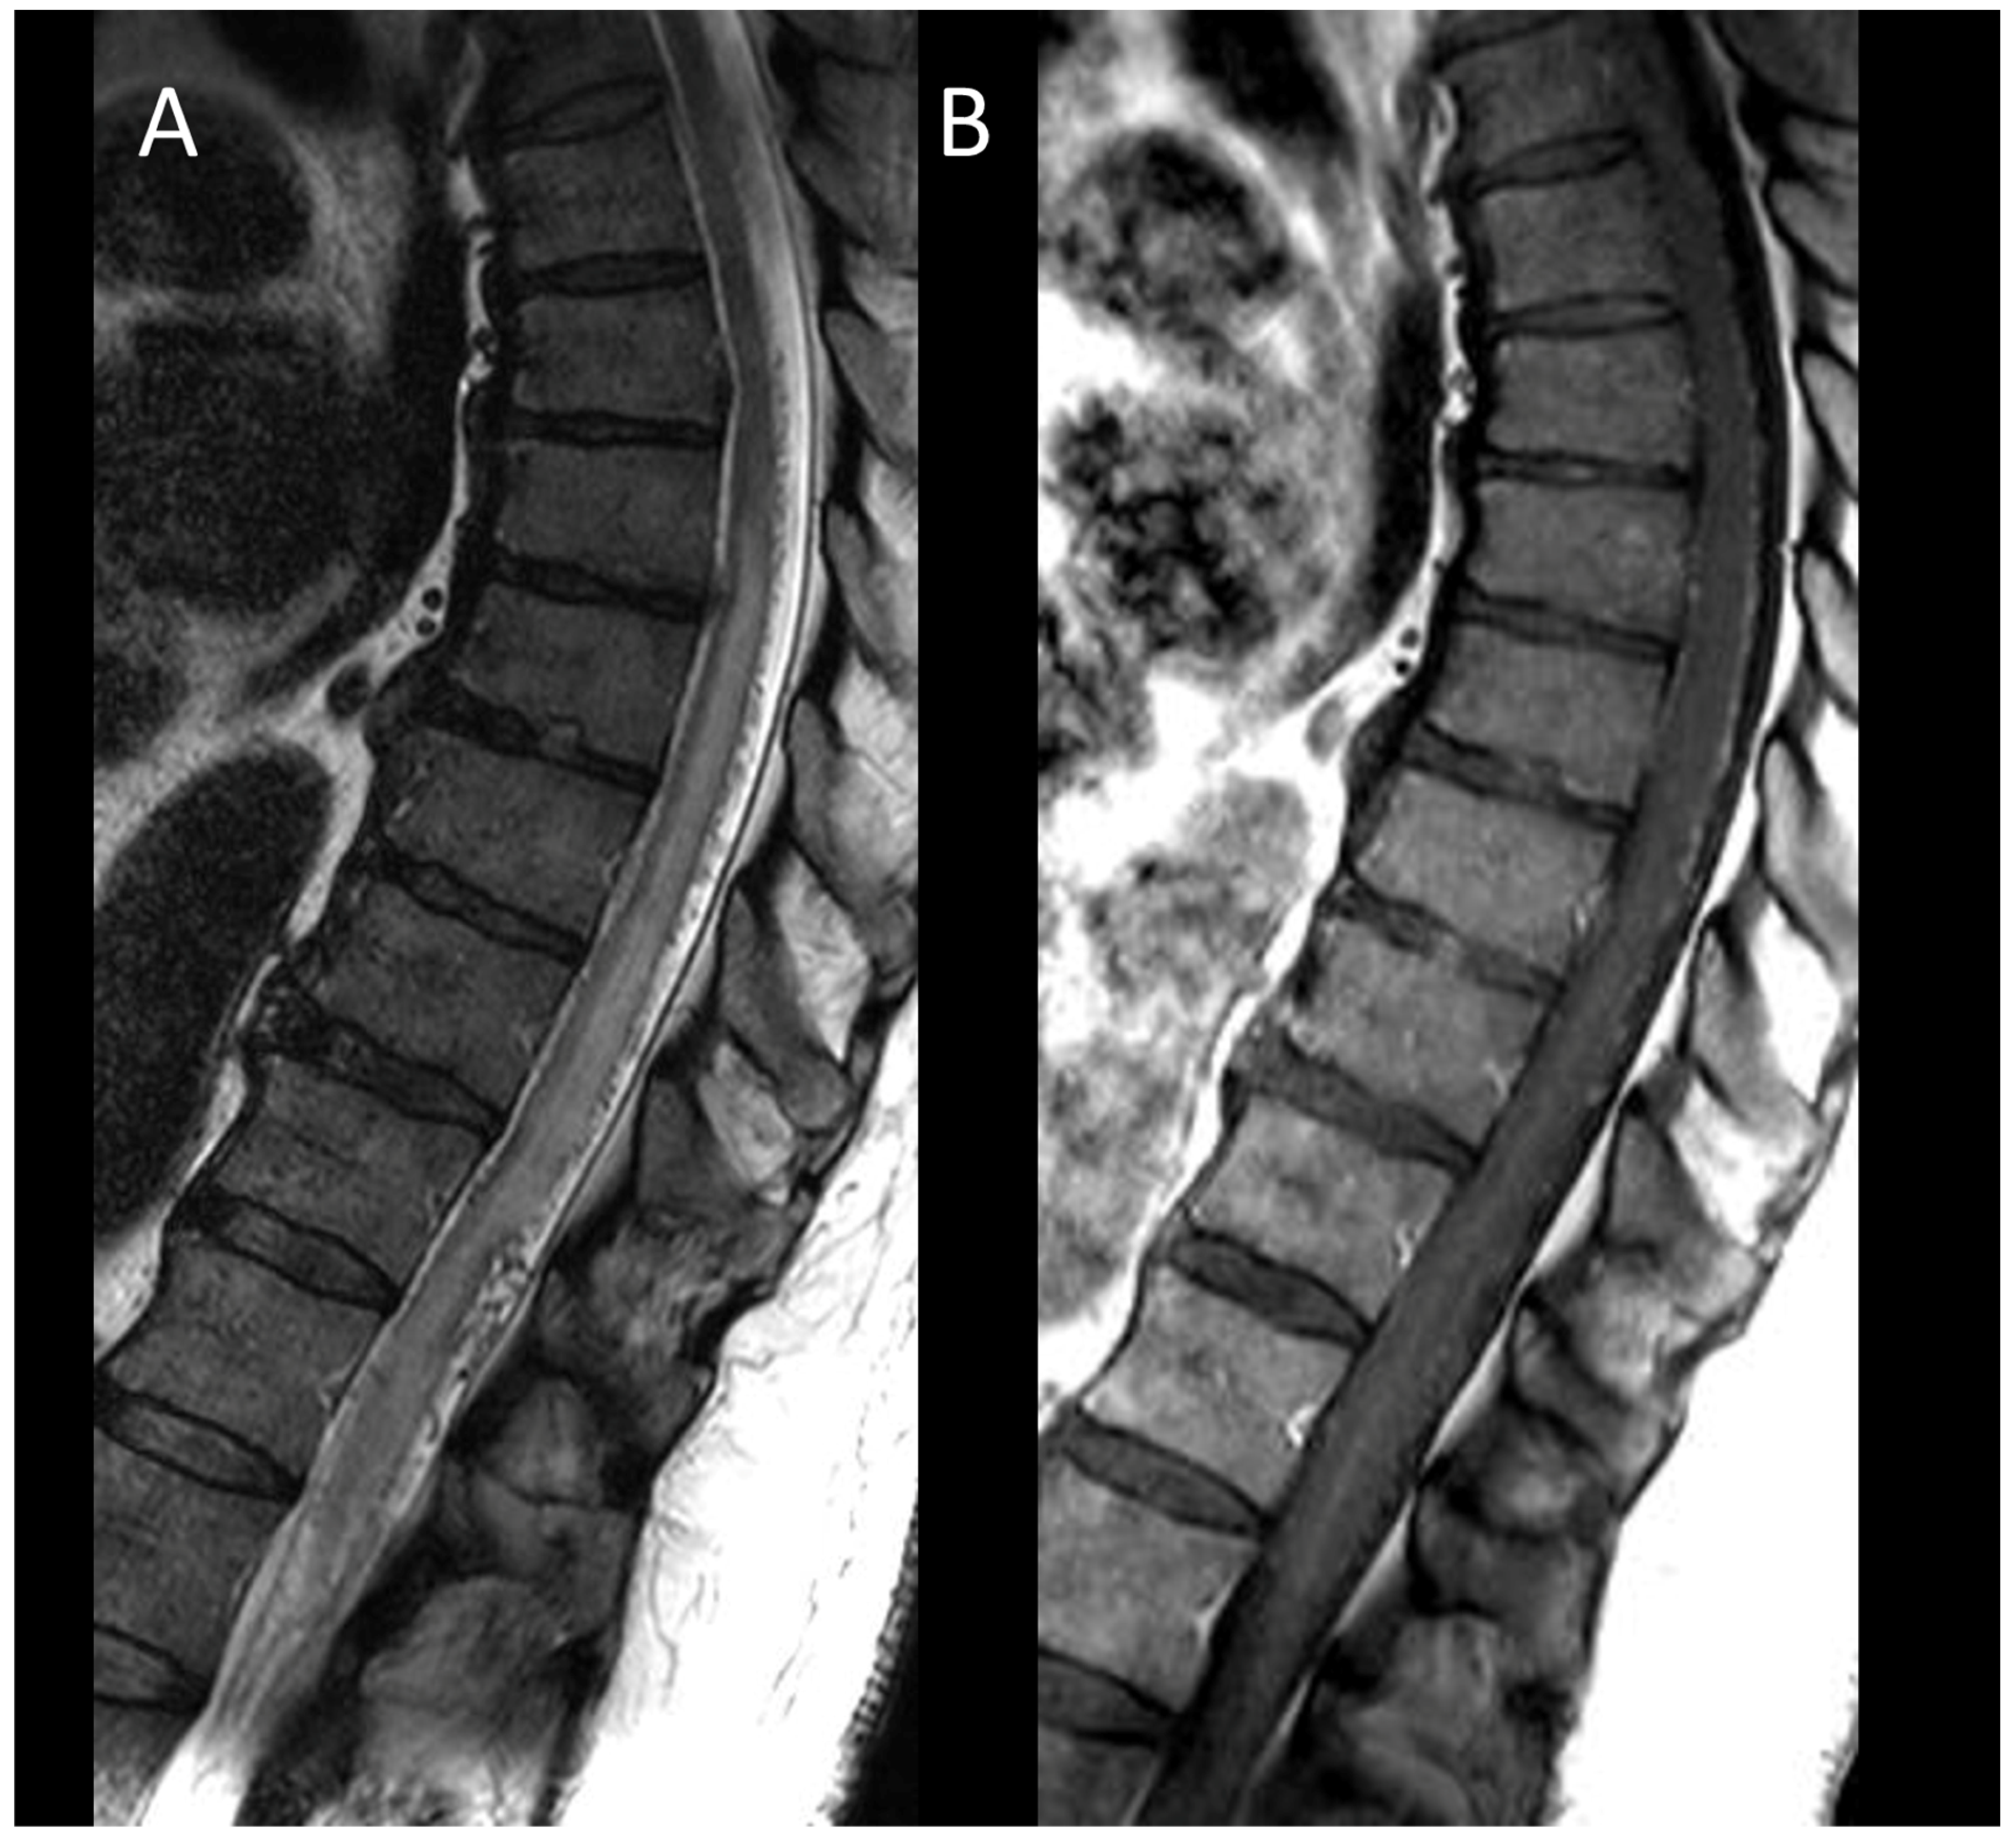

3.3.3. Spinal Cavernous Malformation

3.3.4. Hematomyelia